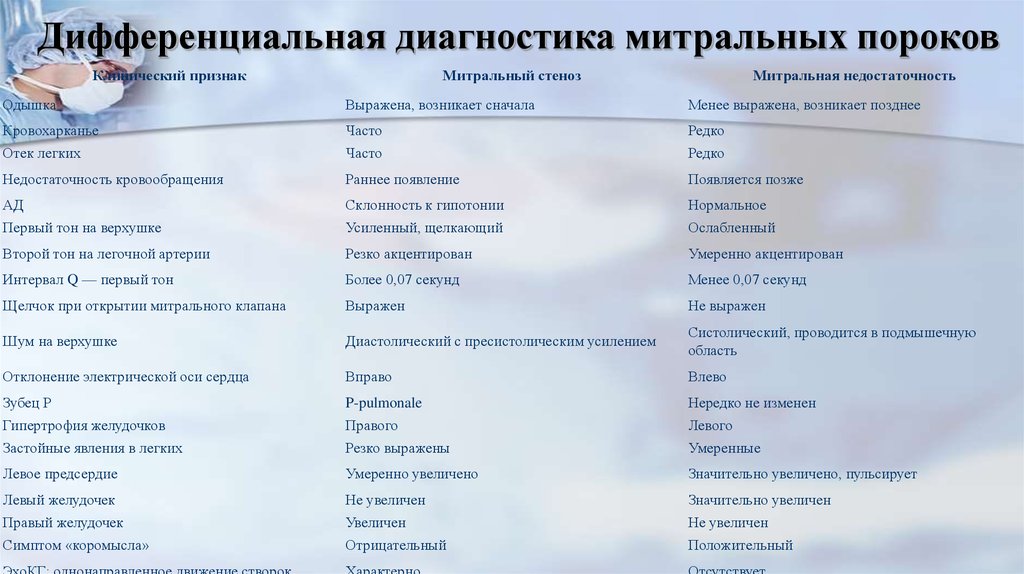

Дифференциальная диагностика заболеваний плевры